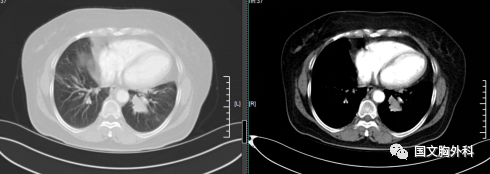

因病灶位置關(guān)系經(jīng)過支氣管鏡檢查未能明確病理,病灶包裹著血管CT穿刺風(fēng)險巨大。